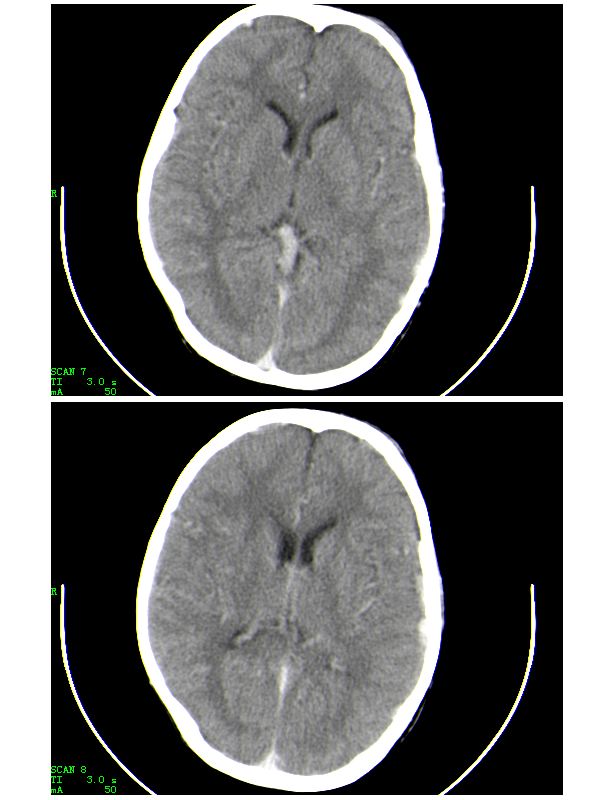

感谢大家的关注,本例我们最后诊断为高血红蛋白症所致的脑血管改变,患者血红蛋白258g/l

下面是第二天的复查和受伤后第五天的复查,左侧硬膜下血肿有所吸收,脑内条状高密度无改变

人体血液中影响ct值的主要成分是有形成分红细胞和血浆中的蛋白质,尤其室含铁的hb,其占血液中蛋白质总量的大部分,亦是引起血液ct密度变化的主要因素。hb含量与ct值间具有相关性,noman等的研究表明hb含量每改变10g/l,相应ct值变化为1.86hu。

本病主要应与蛛网膜下腔出血相鉴别,鉴别要点:

(1)高密度血管网络旁仍见清晰、正常低密度脑脊液影;

(2)临床没有急性颅内出血的症状何体征。